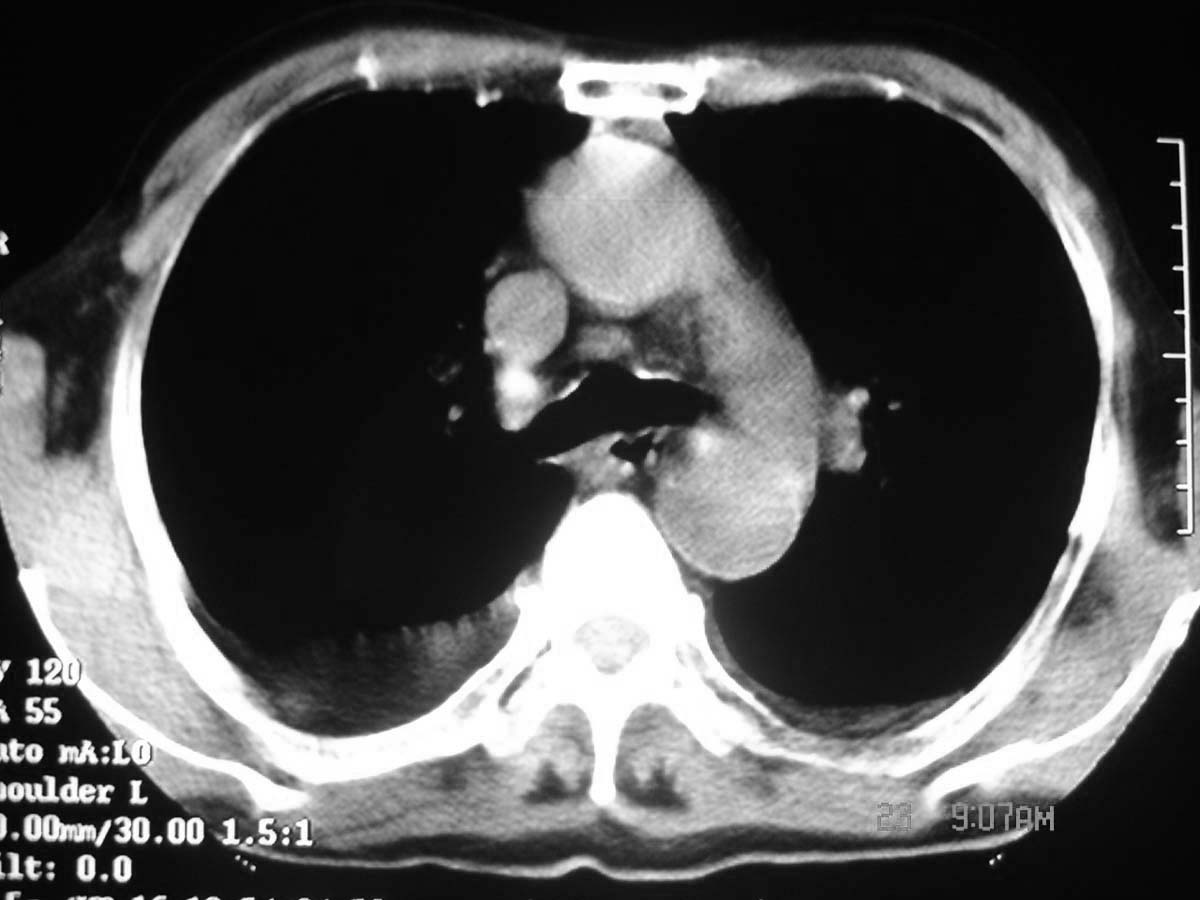

以下是引用守望可可西里在2006-11-23 14:33:00的发言:[br][br] 糖尿病病人很容易继发结核,病人又有双侧胸膜增厚、粘连、胸腔积液以及双上肺的斑片状、条索状影结核病灶影,以一元论考虑,右下肺病变首先考虑干酪性肺炎,可以正规抗炎治疗后复查,排除一般的肺炎。